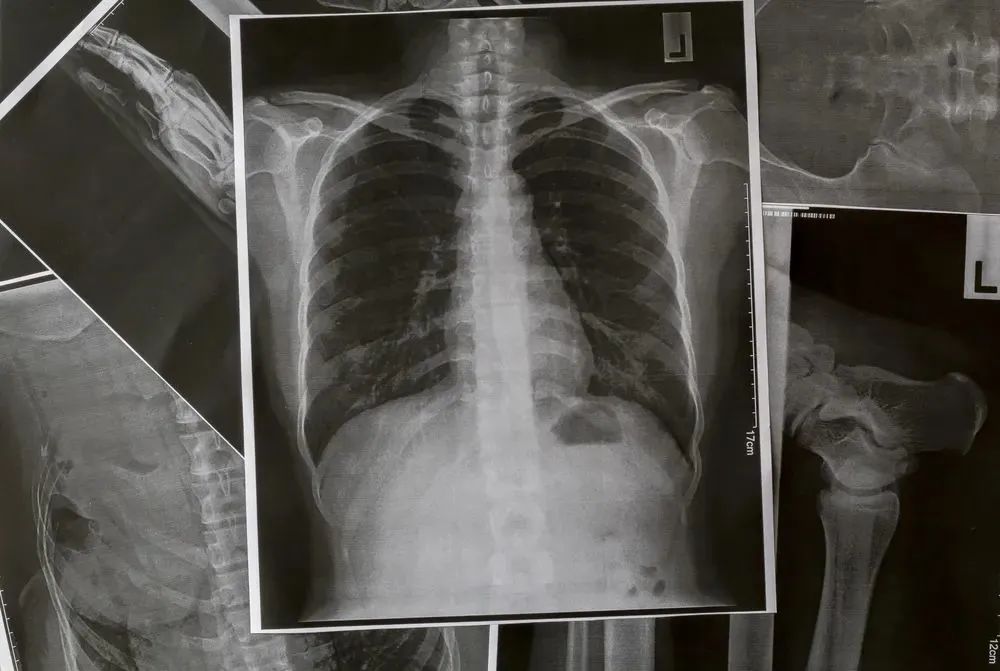

影像科

和全院各大专科都有交集的,除了检验科、病理科,还有影像科。

昏暗的小隔间里面,几十块或横放或竖放的屏幕,一张张没有血与肉的片子正对着黑黑的眼圈和厚厚的镜片,疲惫的人儿流水线般写下一个个描述和诊断,再提交等待上级审核后发布。

有网友吐槽说:影像科是二级科室待遇,一级科室的工作量和要求。干的多挣的却不见得多。

例如某医院影像科取消了夜间加班的额外工作量补助后,真正实现了干的多挣的一样的迷惑操作,夜里的核磁共振也就再也约不到了。